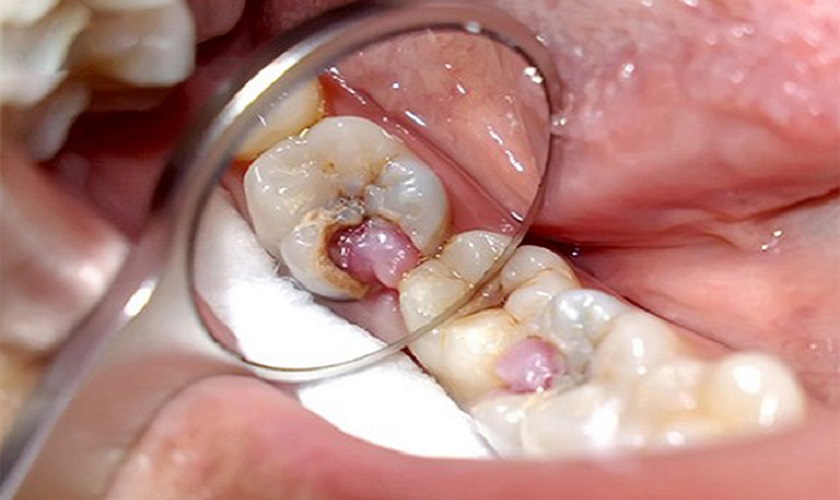

Viêm tủy răng ở trẻ em có thể gây chết tủy và cần được điều trị ngay lập tức. Nếu không, tình trạng đau đớn kéo dài có thể dẫn đến nhiều biến chứng nguy hiểm, thậm chí là mất mạng. Viêm tủy răng là một vấn đề phổ biến ở trẻ em, thường do sâu răng gây ra. Ngoài ra, các chấn thương mạnh như gãy răng, vỡ răng hoặc chảy máu chân răng cũng có thể gây tổn thương cho răng và tạo điều kiện cho vi khuẩn xâm nhập vào tủy răng.

Vậy lấy tủy răng sữa có nguy hiểm không? Vấn đề về việc lấy tủy răng sữa thường khiến phụ huynh lo lắng, lo ngại về ảnh hưởng đến răng vĩnh viễn của trẻ. Tuy nhiên, thực tế việc này không gây ra bất kỳ ảnh hưởng nào đến quá trình mọc lại răng mới. Ngược lại, nếu không điều trị, vi khuẩn từ răng bị chết tủy có thể lan sang các răng khác, phá hủy các mô mềm và tạo điều kiện cho các chất hoại tử tích tụ ở chân răng, gây ra các vấn đề nghiêm trọng như viêm ổ chức liên kết mô – răng, viêm xương hàm, thậm chí là u nang chân răng.

- Nếu răng sữa bị sâu nặng hoặc bị viêm tủy cấp tính, viêm tủy mãn tính hoặc hoại tử tủy răng với các triệu chứng như đau tự phá, sưng, lung lay răng, mủ ở nướu răng thì quy trình thường là lấy tủy toàn phần và trám lại.